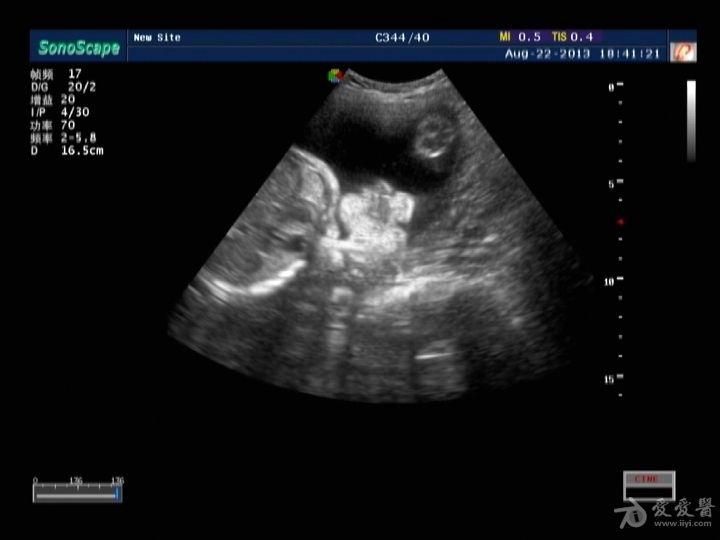

双侧唇裂 ,腭裂, 二维图片 三维图片

胎儿唇腭裂的超声诊断

[产科] 胎儿唇裂